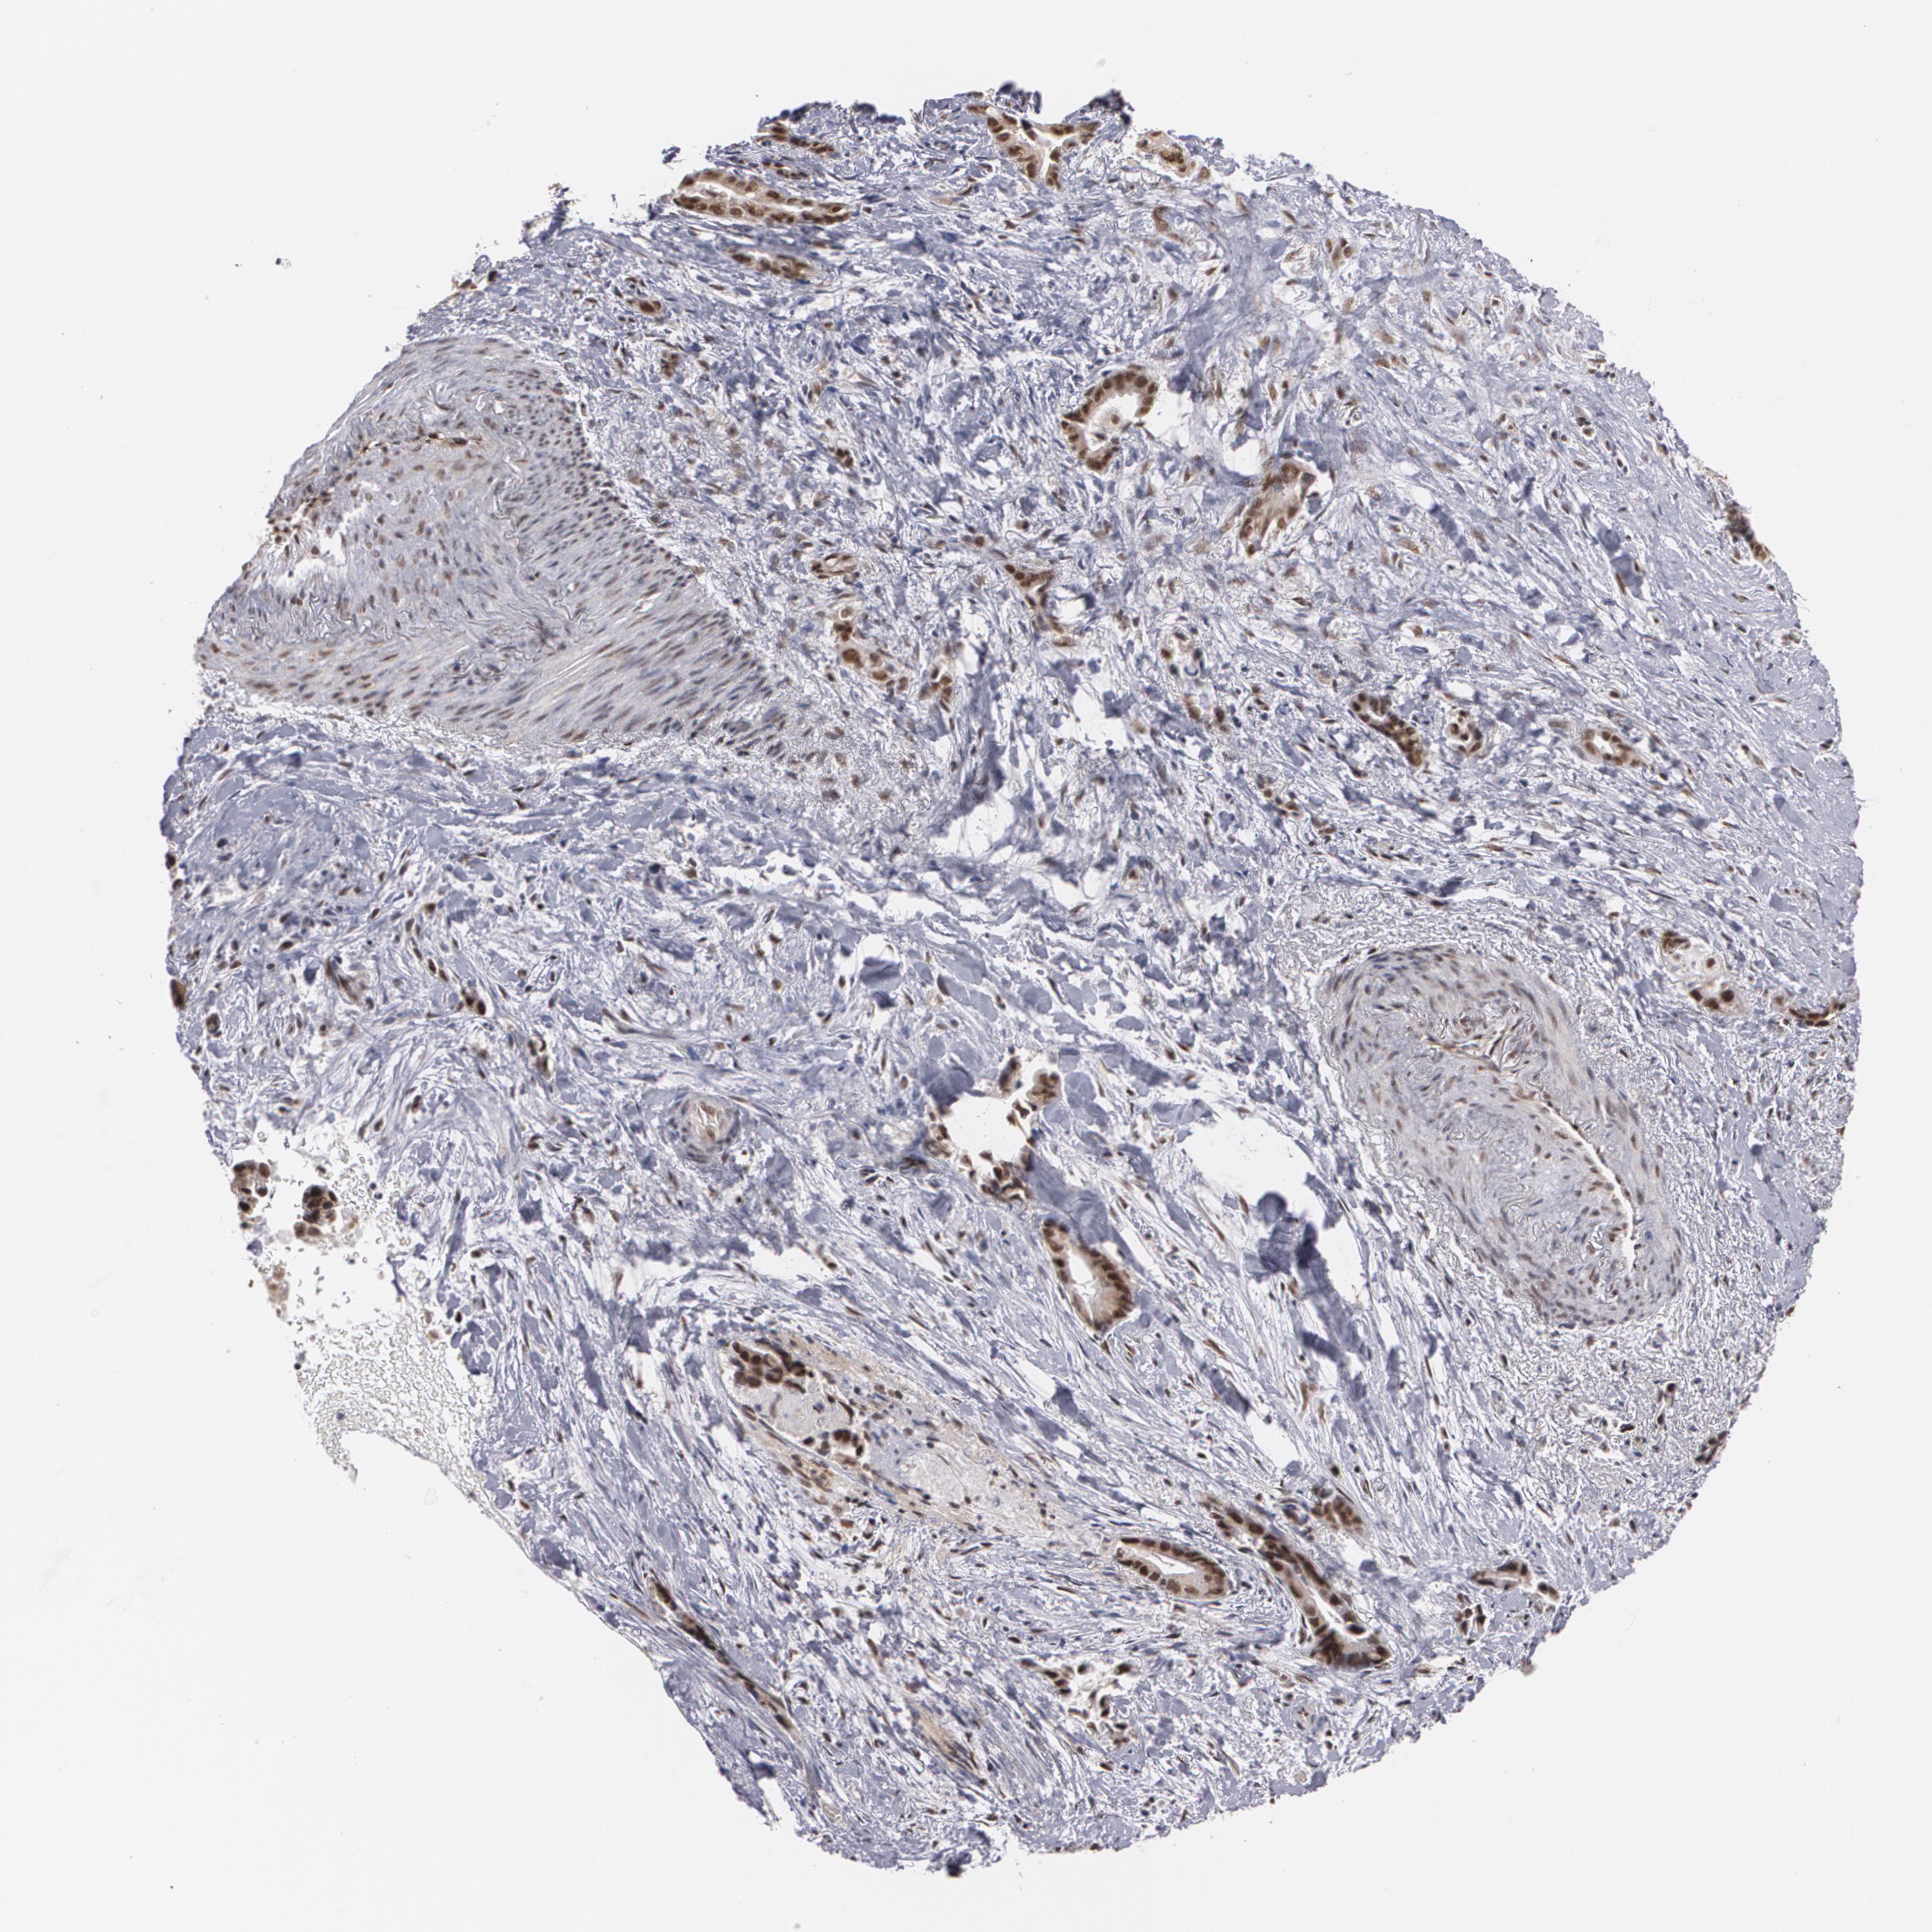

LIVER CANCER - Protein expressioni

A mouse-over function shows sample information and annotation data. Click on an image to view it in a full screen mode. Samples can be filtered based on level of antibody staining by selecting one or several of the following categories: high, medium, low and not detected. The assay and annotation is described here.

Note that samples used for immunohistochemistry by the Human Protein Atlas do not correspond to samples in the TCGA dataset.

Antibody stainingi

Antibody staining in the annotated cell types in the current human tissue is reported as not detected, low, medium, or high, based on conventional immunohistochemistry profiling in selected tissues. This score is based on the combination of the staining intensity and fraction of stained cells.

Each image is clickable and will lead to virtual microscopy that enables deeper exploration of all samples and also displays staining intensity scores, fraction scores and subcellular localization as well as patient and tissue information for each sample.

Antibody HPA001665

Staining

High

Medium

Low

Not detected

Intensity

Strong

Moderate

Weak

Negative

Quantity

>75%

75%-25%

<25%

None

Location

Nuclear

Cytoplasmic/membranous

Cytoplasmic/membranous,nuclear

Cholangiocarcinoma

Carcinoma, Hepatocellular, NOS